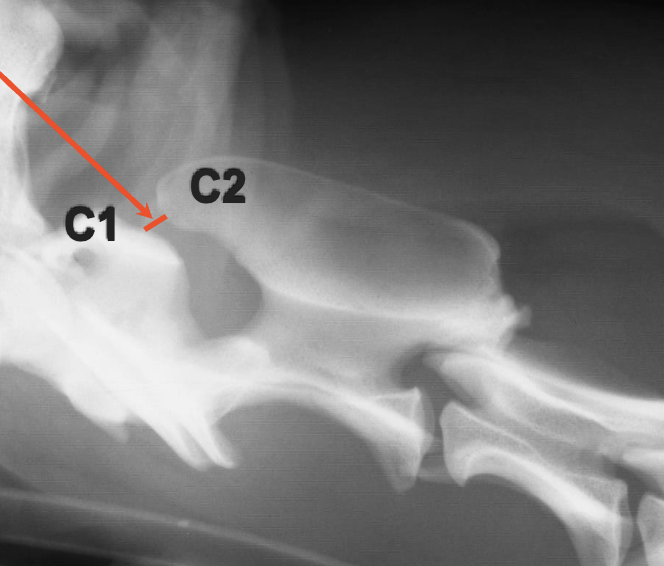

What is shown in this image?

AA joint with normal space between C1 and C2